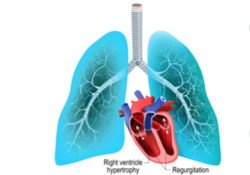

PH heeft zowel gevolgen voor de longen als voor het hart. Vanuit de rechterkamer van het hart wordt er bloed naar de longen gepompt. De linkerkamer van het hart pompt bloed naar de rest van het lichaam. Door de hoge druk in de longvaten moet de rechter hartkamer veel harder werken om bloed naar de longen te krijgen. Het rechterhart zet zich uit en kan steeds minder bloed pompen. Na verloop van tijd gaat het rechterhart op het linkerhart drukken, zodat er ook minder bloed naar de rest van het lichaam wordt gepompt. Er ontstaat uiteindelijk hartfalen.